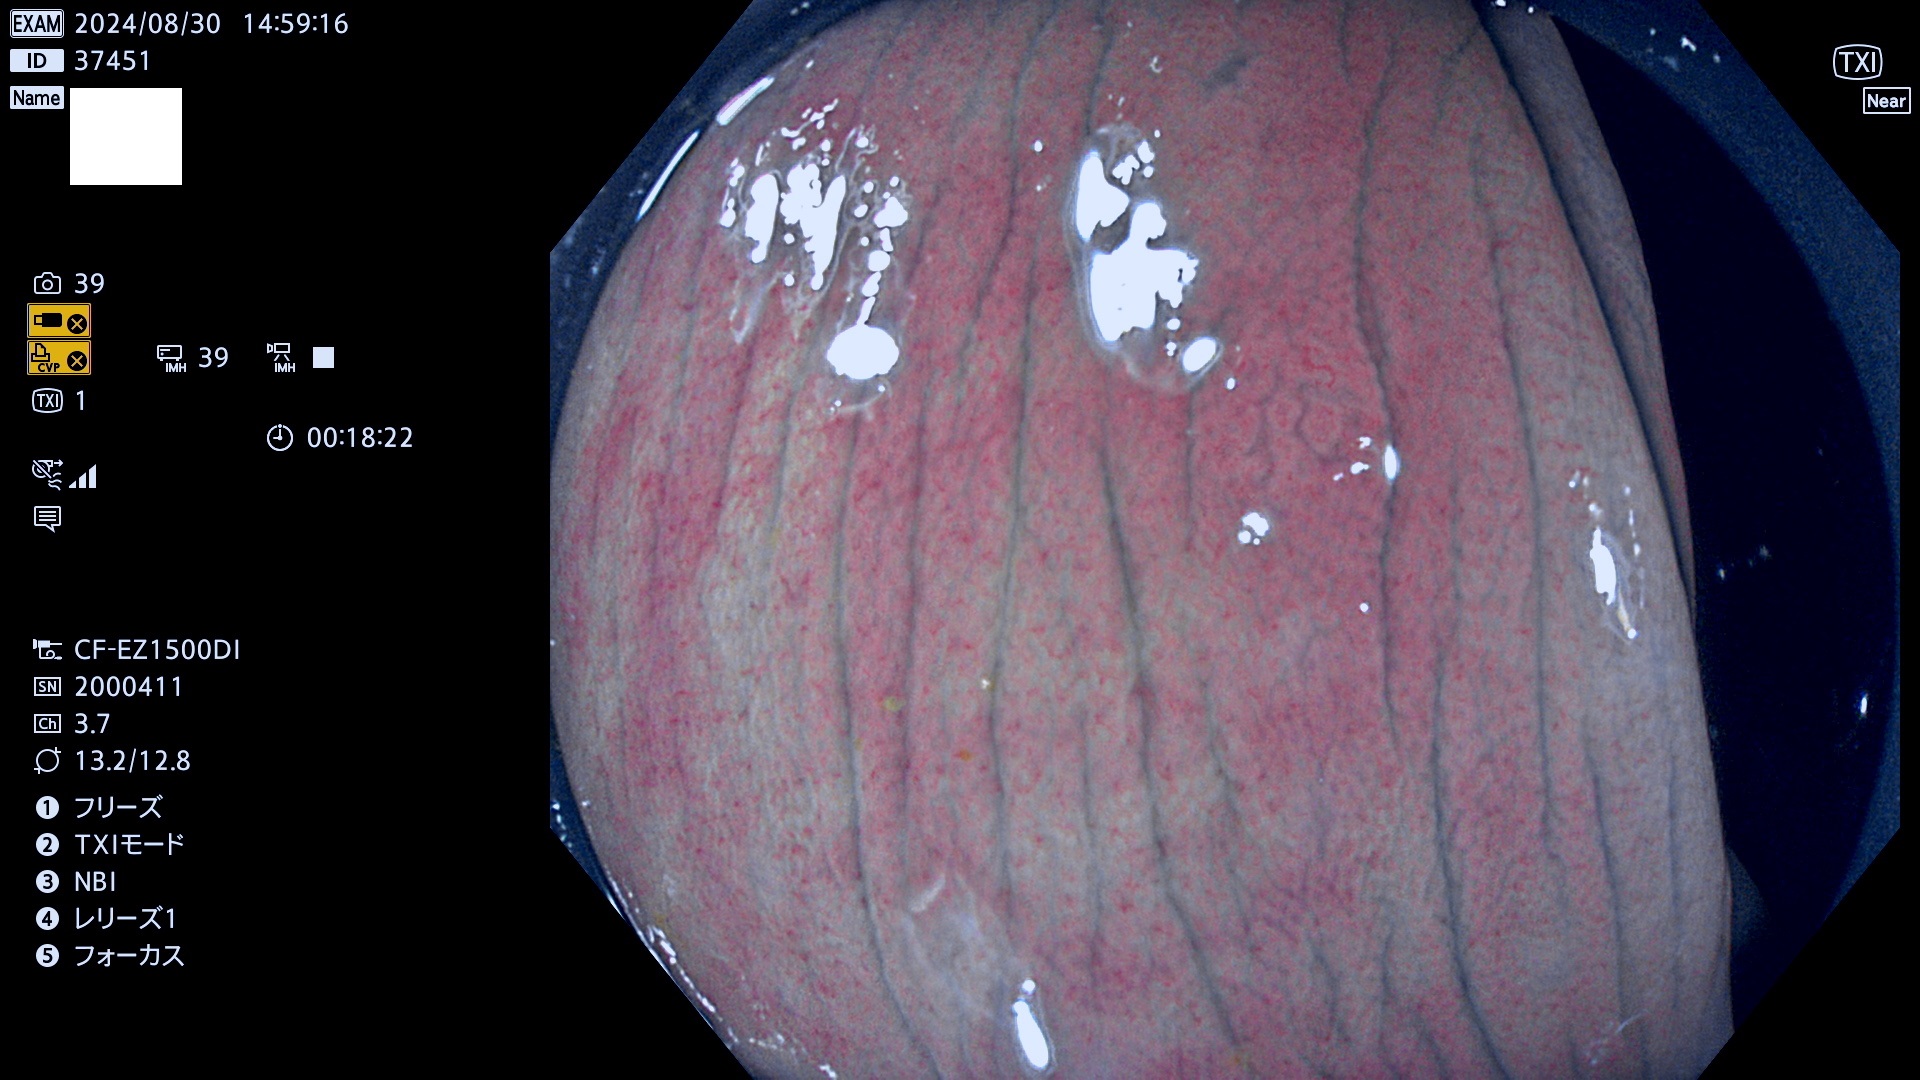

完全に平坦な物をUb、陥凹している物をUcと呼びます。最も発見が難しく危険な病変です。

抽出の対象期間 2024年8月29日〜9月1の4日間(40件の検査)5件 (5/40=13%)